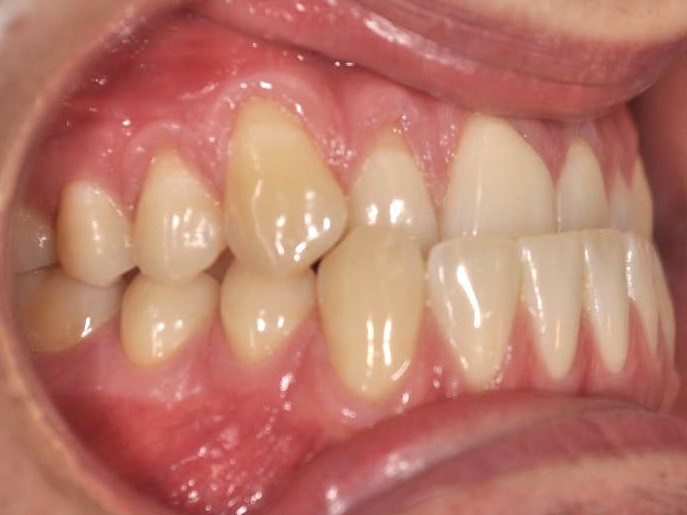

L’examen endobuccal

En intra-arcades (fig. 4-6), on note une classe III molaire et canine (fig. 4-5), trois plans d’occlusion, une déviation des milieux d’origine mandibulaire et un inversé articulé du bloc incisif maxillaire ; le biotype parodontal est fin, et l’on note des récessions gingivales (12, 13, 23, 33, 43) certainement dues à la mauvaise position et aux forces mal réparties lors de la mastication (fig. 5). L’arcade maxillaire est carrée avec une DDM antérieure (fig. 7), l’arcade mandibulaire étroite et allongée (fig. 8).